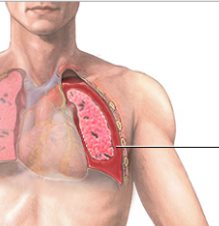

Hemotórax

El objetivo del tratamiento es estabilizar al paciente, detener el sangrado y extraer la sangre y el aire del espacio pleural. Se introduce una sonda pleural a través de la pared del tórax con el fin de drenar la sangre y el aire. La sonda se deja puesta durante varios días para volver a expandir el pulmón.